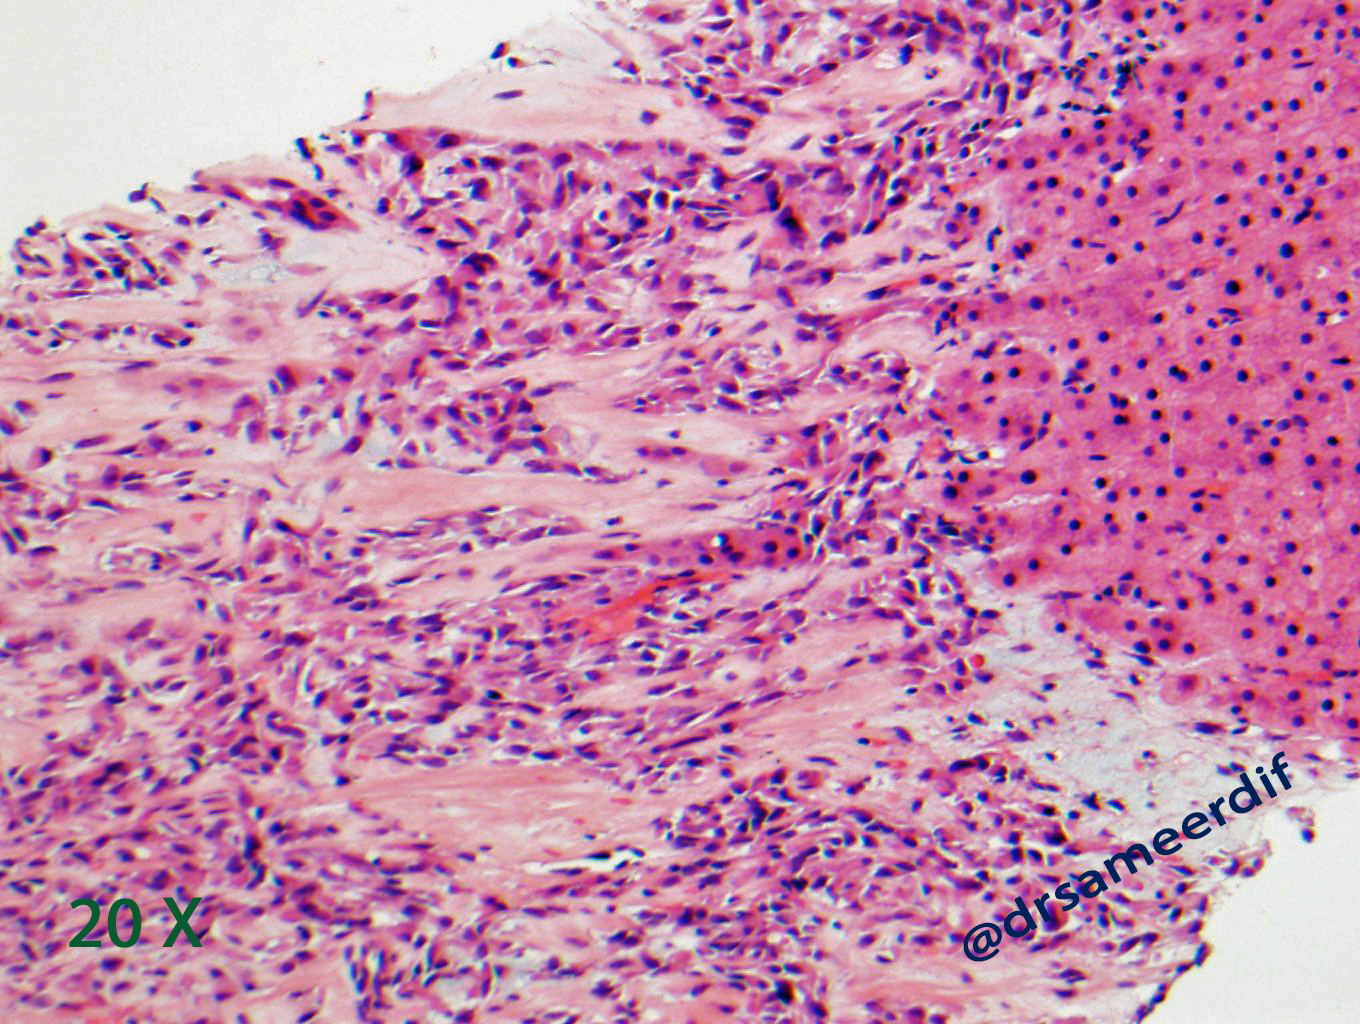

The current biopsy shows a densely hyalinized sclerotic matrix, with focal areas reminiscent of osteoid, lined by small to medium-sized epithelioid cells with clear to eosinophilic cytoplasm and bland nuclei. Mitotic figures are inconspicuous. By immunohistochemistry, the neoplastic cells are positive for MUC4, but negative for CK7, CK20, SATB2, and calcitonin. The morphology and immunohistochemical results are diagnostic of metastatic sclerosing epithelioid fibrosarcoma (SFE) from primary know SFE of the soft tissue.

- Nests and cords of small to medium size, round- oval nuclei with scant clear to pale cytoplasm

- Hyalinized stroma, which may resemble osteoid. Sometimes cartilaginous and osseous metaplasia may be seen and it may show focal myxoid change or calcification.